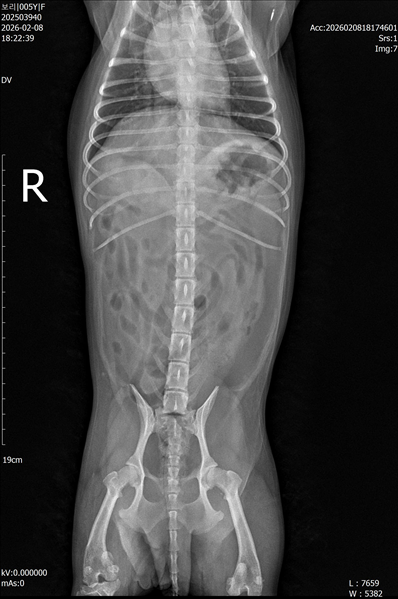

강아지 슬개골탈구 진단 받았습니다 몇군데 병원을 다녀봤는데 진단이 달라 궁금해서 질문 해봅니다 일단 저희 강아지는 오른쪽 다리를 갑자기 들고 다니고 절어 병원을 방문하게 되었고요 왼쪽은 증상이 없지만 오른쪽만 있는 상태였습니다 첫번째랑 두번째 병원에서는 슬개골 탈구 진행중이고 왼쪽이 3기 오른쪽이 2기 정도라고 했습니다 하지만 왼쪽은 아예 빠져있어 증상도 없고 아파하지도 않는다고 했고 오른쪽은 빠졌다 안빠졌다 해서 증상이 있다고 했고 십자인대가 파열된 걸론 보이지 않는다고 했습니다 그래서 양쪽 슬개골탈구 수술만 진행하면 된다고 했고요 근데 세번째 병원에서는 둘다 왼쪽이 좀 더 심한 슬개골 탈구 3기 정도라고 했고 오른쪽만 십자인대 부분파열이 보인다고 했습니다 그래서 십자인대 파열이 아닌 왼쪽은 굳이 수술할 필요가 없고 나중에 십자인대 파열이 오거나 증상이 나타나면 그때 수술하면 된다고 했습니다 그래서 오른쪽 슬개골탈구 수술과 tplo를 하는 방식으로 수술을 한다고 했습니다 여기서 궁금한점은